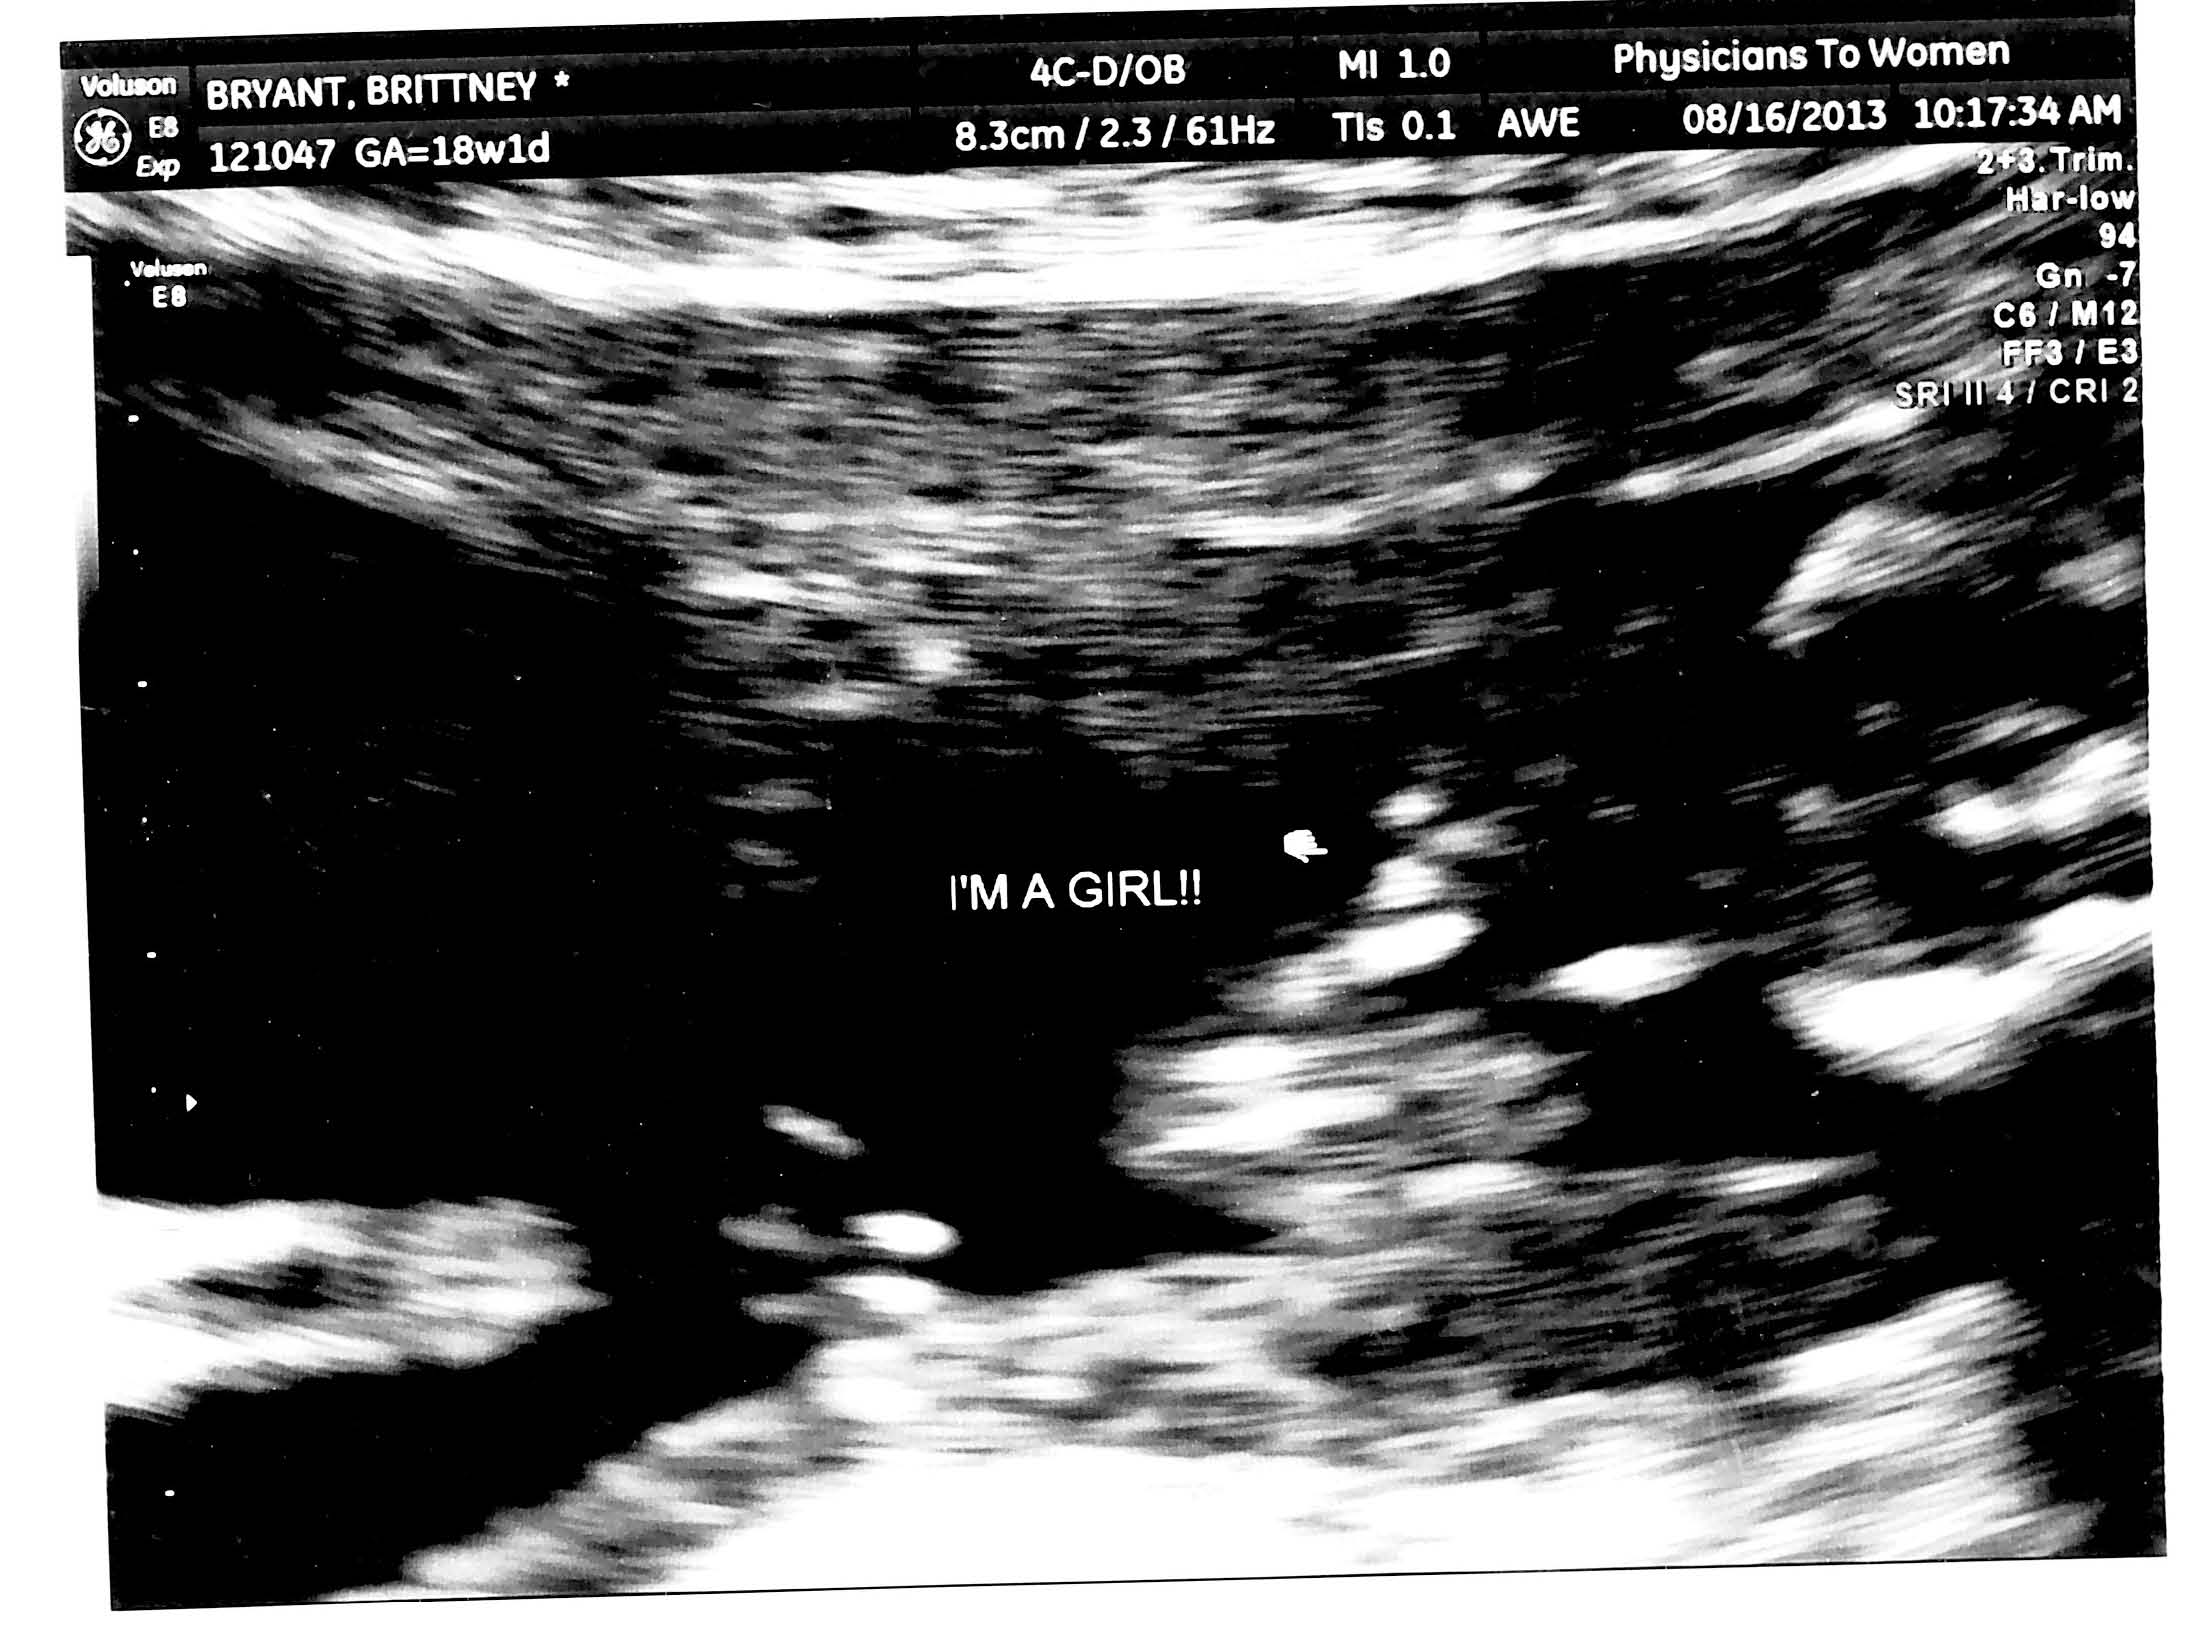

I am 20 weeks today and we had our last ultrasound at 18 weeks and 1 day. My doctor doesn't plan on scanning me again until mid October. They did measurements and blood flow scans then as well. They didn't get a perfect shot of the face, which I remember the tech saying...she might wanna rescan for a better shot of the face. Should I ask for another scan before that to recheck development and gender?? Can the gender be questionable at that stage?? She told me she saw no boy parts at all. We go back for a regular appt on Sept 12th. Advice pleace??

• Here is the gender photo....does this help????

That kind of looks like my baby girls ultrasound.  I know at my OB office you can pay $30 to have a quick gender scan.  Maybe your office does something like that.